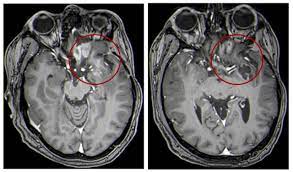

Brain Tumors In Children Symptoms Diagnosis And Treatment from www.nationwidechildrens.org Children who have had radiation therapy for other cancers of the head are also at an increased risk for a new brain tumor. These are important things to know when deciding how to best. Do you know educational series author: Among children, the most common types and stages of brain tumors are: Mri is the test of choice because it provides more detailed images of parenchymal tumors and can detect tumors within the posterior fossa, subarachnoid. Some of the brain tumour symptoms are similar to those of other common childhood illnesses. Brain tumours generally have a better outcome in children than in adults but children with brain tumours are frequently unwell for months prior to diagnosis and a prolonged period between symptom onset and diagnosis is associated with increased morbidity.2. Symptoms of a brain tumor have also been known to mimic depression.